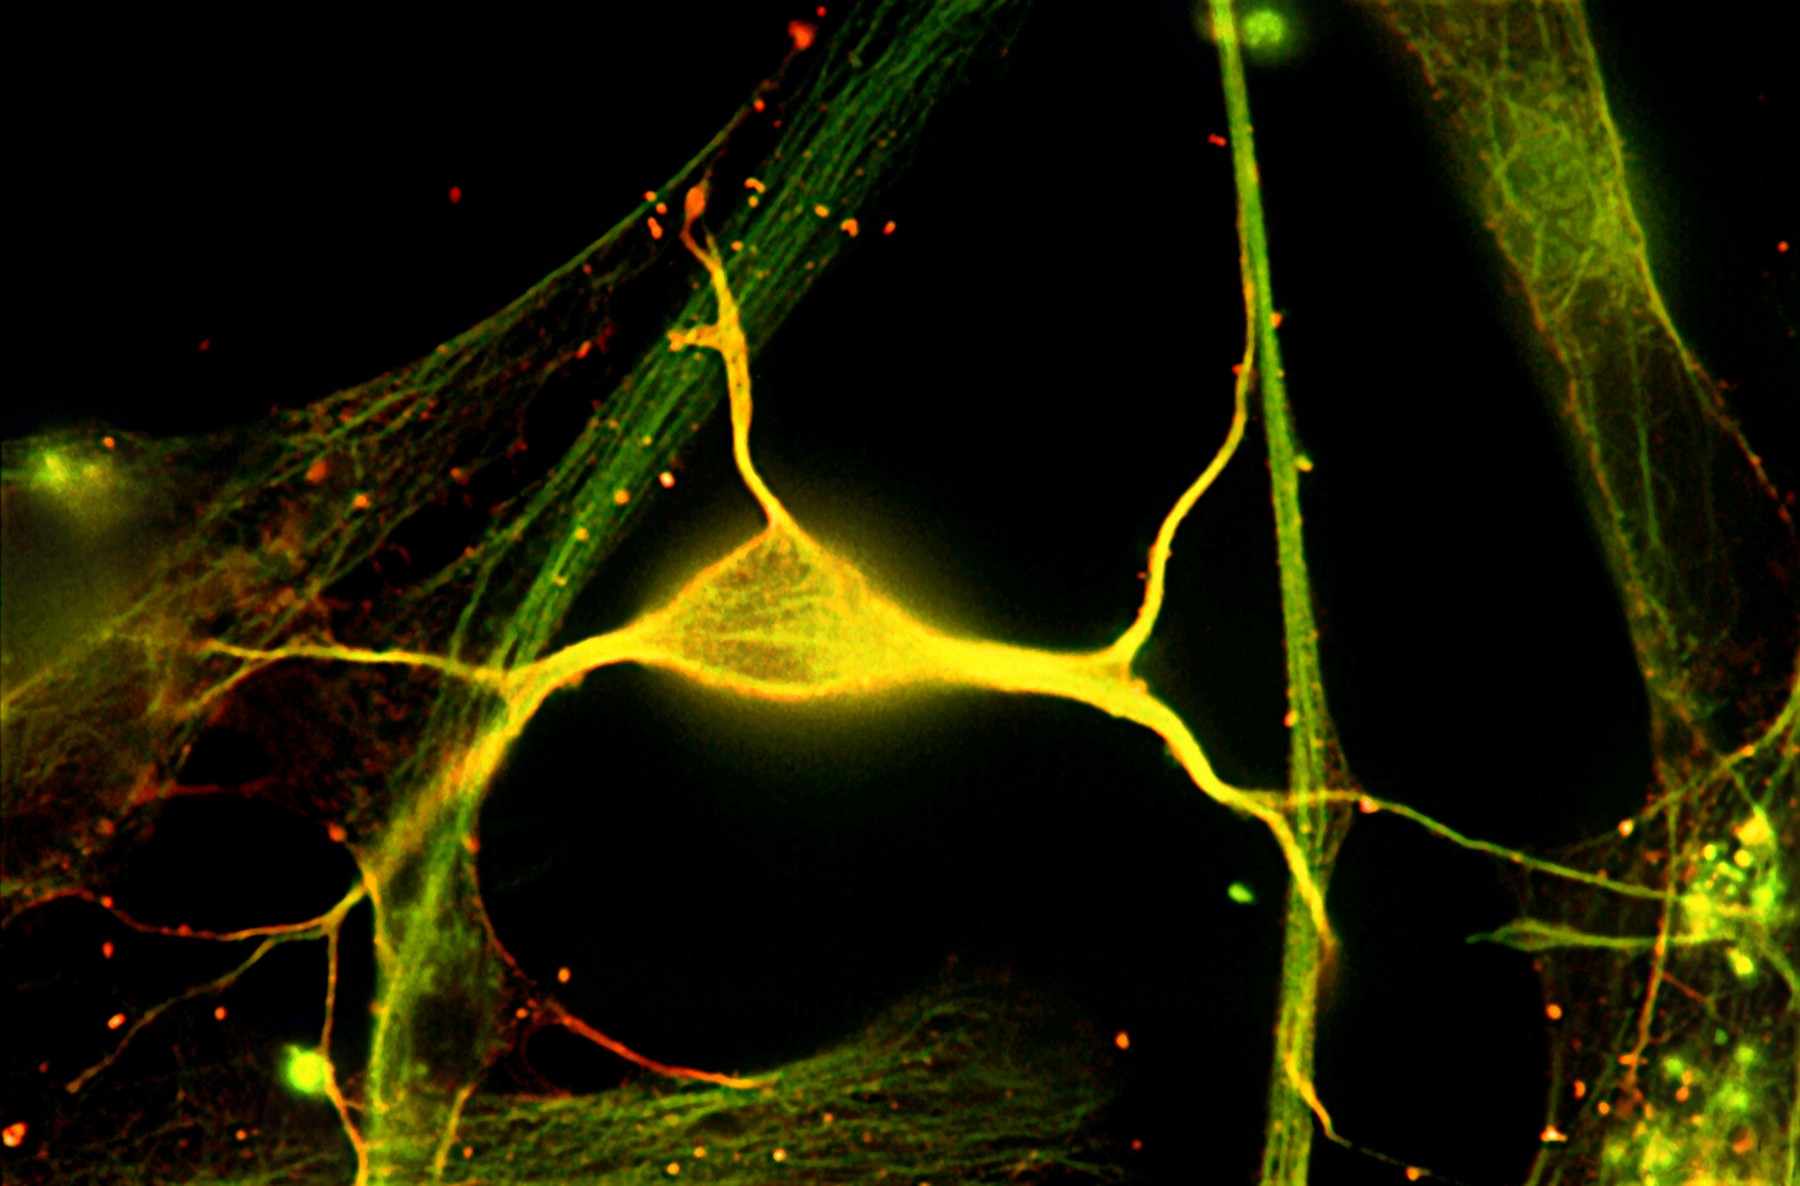

neuroniFoto: ROBERT MCNEIL, BAYLOR COLLEGE OF MEDICINE / Sciencephoto / Profimedia